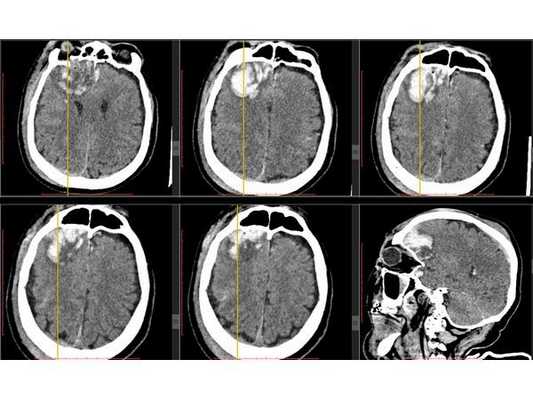

На контрольной КТ головного мозга в послеоперационном периоде видна положительная динамика: состояние после краниотомии, репозиции вдавленных фрагментов теменной кости, удаления субдуральной гематомы, регресса дислокации срединных структур стабильное.

После операции состояние пациента постепенного восстановилось до ясного. На третьи сутки после операции проведена контрольная КТ головного мозга. Также пациент был оперирован по поводу скелетной травмы, деканулирован на восьмые сутки после операции. Операционная рана и трахеостома зажили.